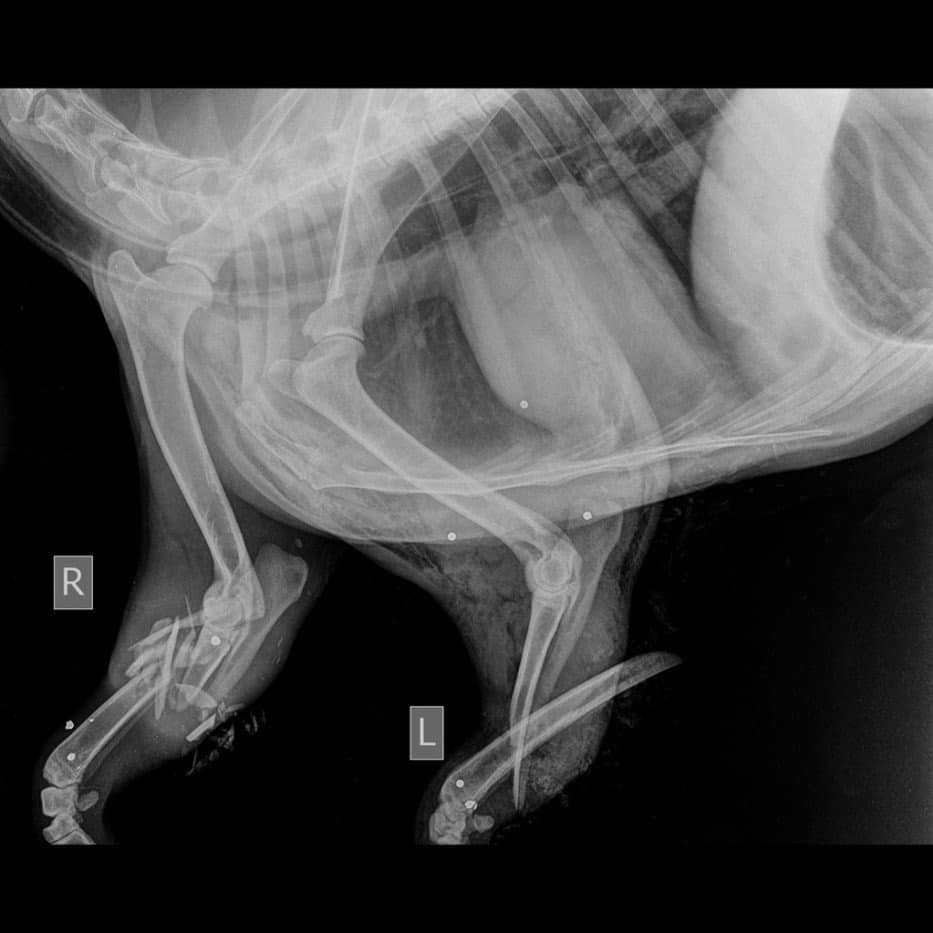

Από τις ακτινογραφίες που του έγιναν διαπιστώθηκε ότι το ζαρκάδι είχε πυροβοληθεί από λαθροθήρα και στα δύο μπροστινά του άκρα, όπου και έφερε συντριπτικά κατάγματα. Η κατάστασή του, δυστυχώς, ήταν μη αναστρέψιμη με αποτέλεσμα να γίνει ευθανασία.

Η ακτινογραφία